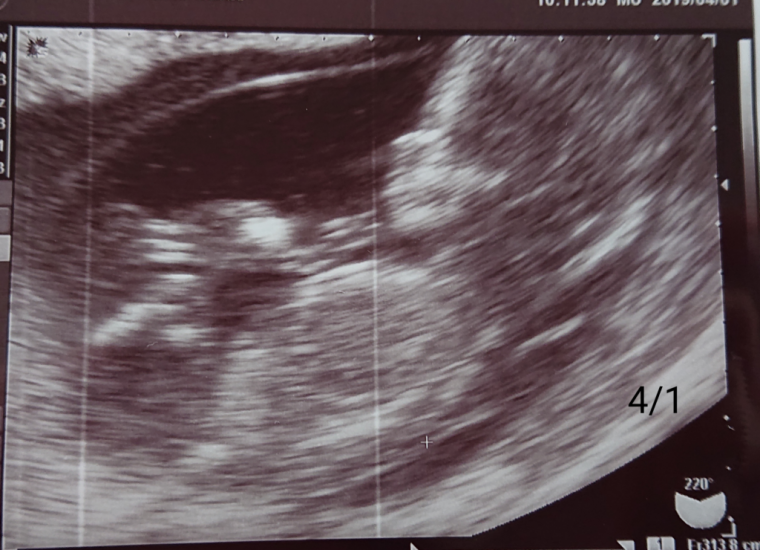

妊娠14週 3 6日 のエコー写真 体験談

妊娠14週 0 2日 のエコー写真 体験談

妊娠14週 赤ちゃんのエコー写真 超音波写真まとめ たまひよ

妊婦健診 14週 エコー写真あり にくまん Note

妊娠14週1日 14w1d の超音波 エコー 写真

妊娠14週 赤ちゃんのエコー写真 超音波写真まとめ たまひよ

妊娠14週 赤ちゃんのエコー写真 超音波写真まとめ たまひよ

育児日記 新米パパの記録 妊娠14週目の超音波写真

妊娠14週 赤ちゃんのエコー写真 超音波写真まとめ たまひよ

妊娠14週目 14w0d 6d のエコー写真とエピソード 妊娠4ヶ月 Cozre コズレ 子育てマガジン

妊娠14週 赤ちゃんのエコー写真 超音波写真まとめ たまひよ